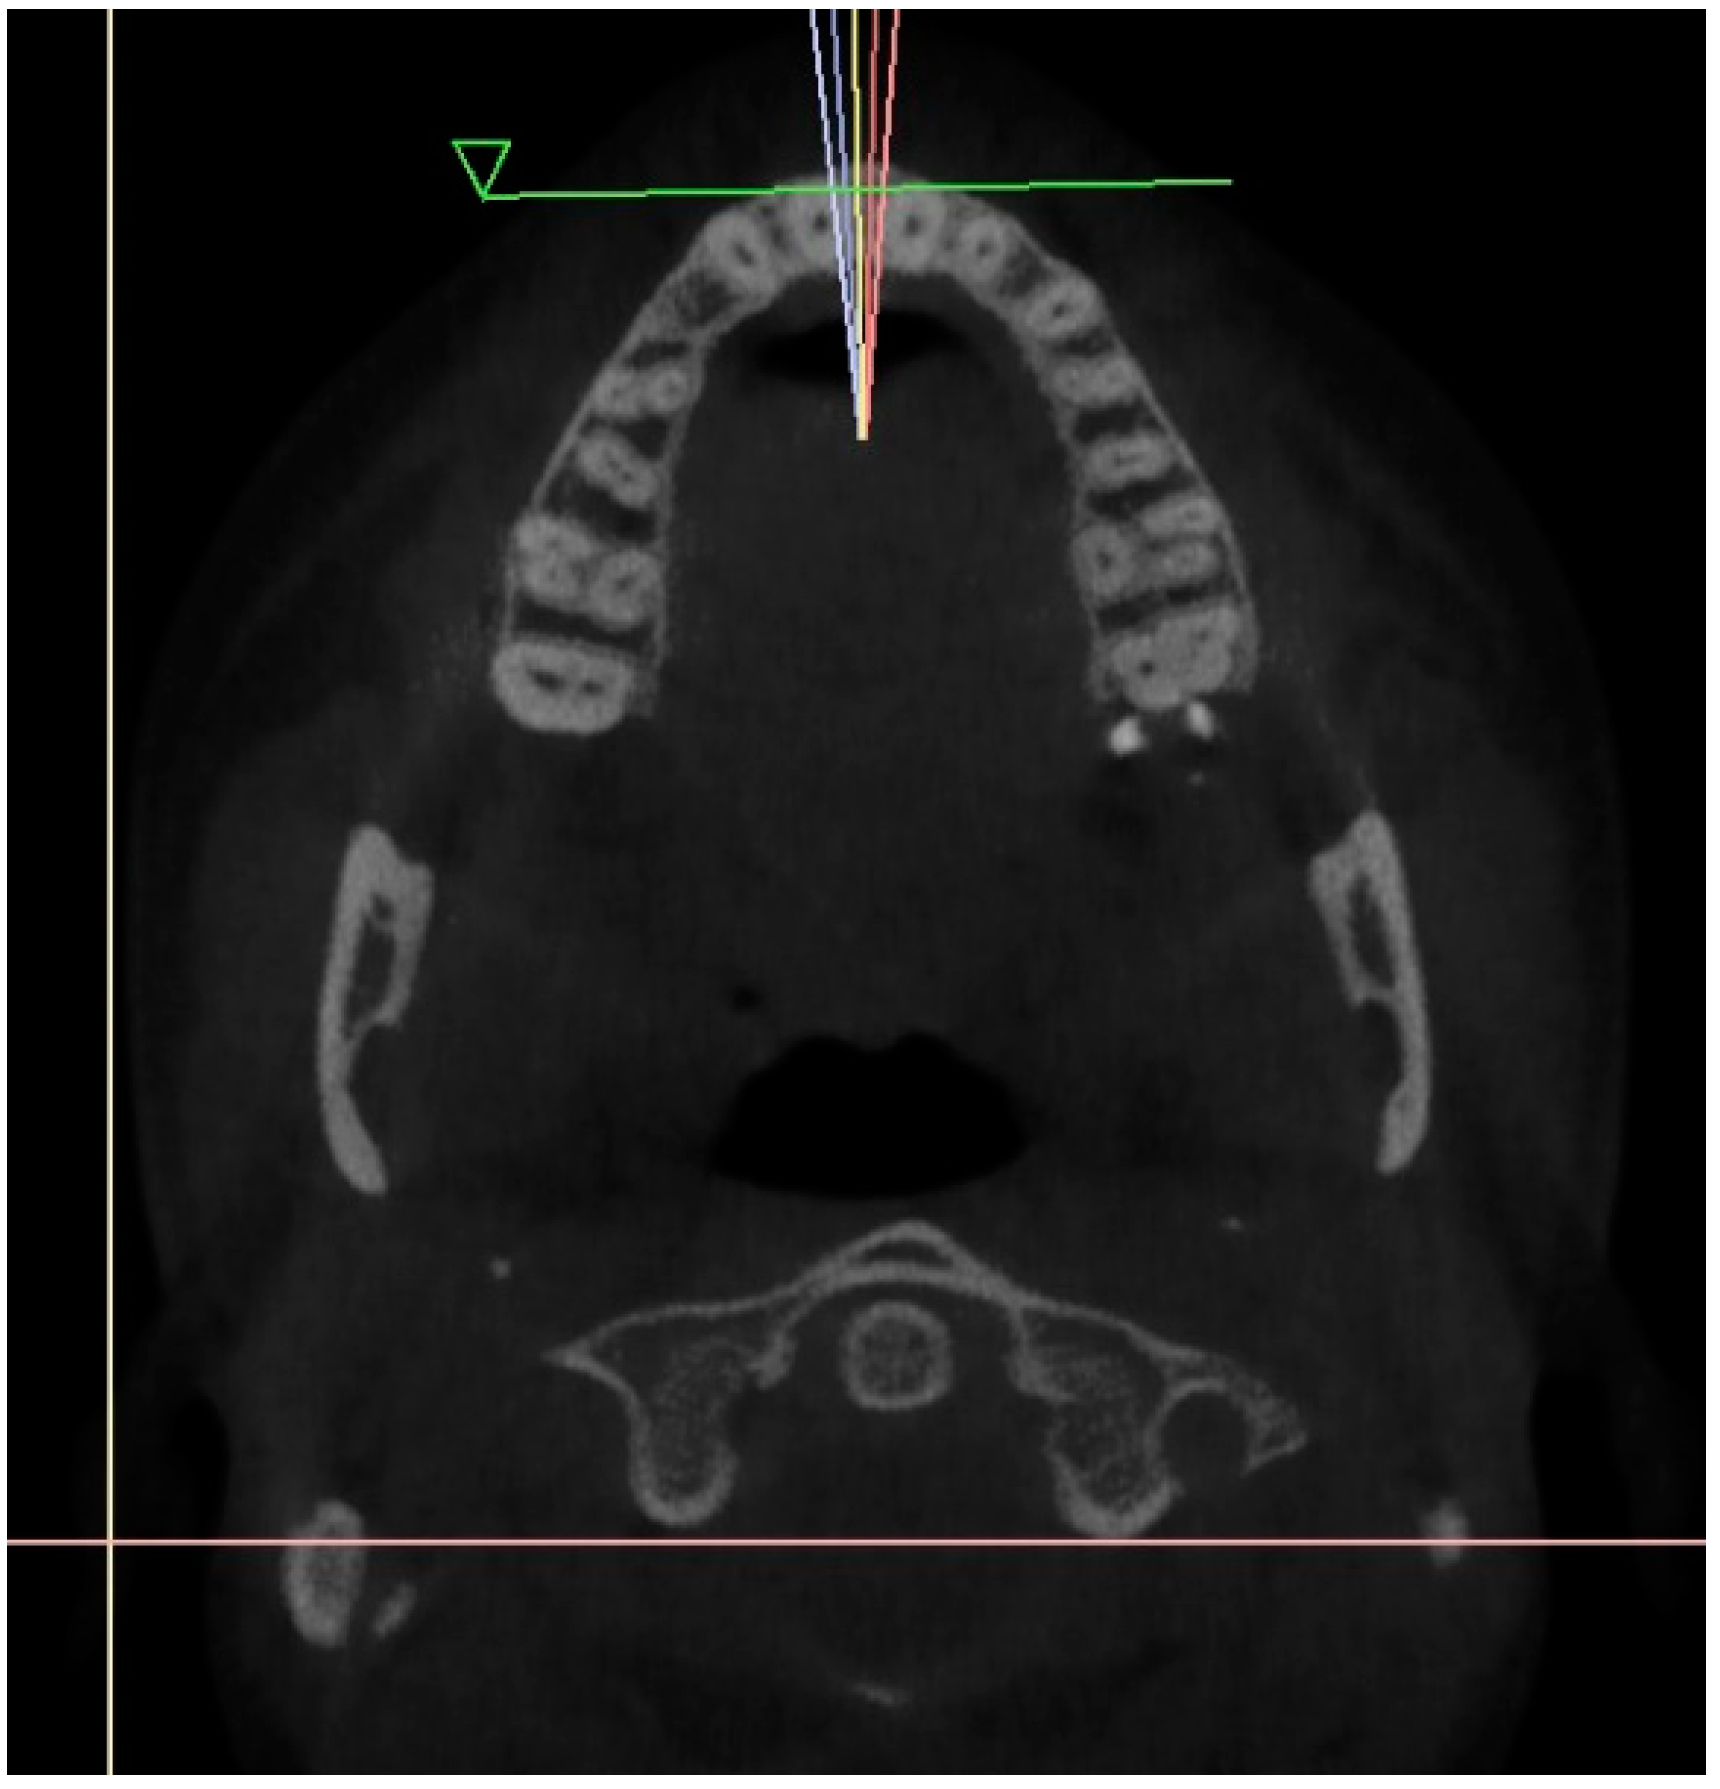

Initially, a panoramic image of patients was used for a general dental evaluation and select cases according to inclusion criteria as shown in Figure 2. An axial view of the maxillary arch was used to evaluate the number of roots and canals in maxillary molars as shown in Figure 3. Subsequently, the coronal view was used to evaluate the type of Vertucci’s classification in the palatal root of maxillary first molar as shown in Figure 4.

Figure 3.

Axial view of maxillary arch showing number of roots and canals in maxillay molars.